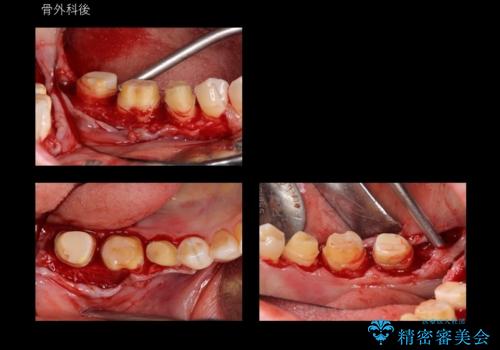

奥歯の高さがない 歯周外科で解決

- 右下奥歯(7番)の高さがなく、かぶせ物(クラウン)にするためにあらかじめ歯周外科手術を行いました。(クラウンレングスニング)

右下5番は歯ぐき付近までWSD(くさび状欠損)で削れていたため、患者様と相談してクラウンにしました。その際、削れていたのが歯肉縁下に及んでいたため、一緒に手術範囲に含めました。

歯の高さを出すとかぶせ物(クラウン)がはずれにくくなります。